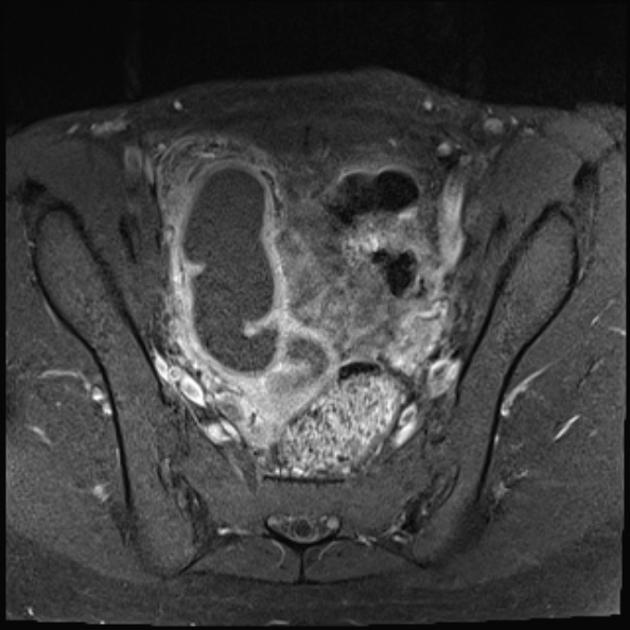

Keputusan yang dibuat pada hari ini boleh membawa implikasi besar dalam hidup mereka, kisah yang didedahkan seorang doktor ini wajar dijadikan peringatan bersama. Difahamkan, seorang pelajar berusia 16 tahun dibawa ibu bapanya ke hospital atas keluhan mengalami haid berpanjangan dan rasa tegang di bahagian perut. Disangka sekadar gangguan hormon, hasil imbasan USG akhirnya mendedahkan isu lebih besar.

Rupa-rupanya, remaja berkenaan mengalami jangkitan di organ reproduksi yang dikenali sebagai Pelvic Inflammatory Disease (PID). Setelah ditanya lebih lanjut, barulah dia mengaku tentang kekerapan melakukan hubungan dengan teman lelakinya. Bermula dengan masalah keputihan melampau, kuning dan berbau, jangkitan kelamin itu mula tersebar ke bahagian lain.

Bagi rawatan susulan, doktor terpaksa memberikan dos antibiotik yang cukup tinggi kepada remaja berkenaan. Jika jangkitan itu semakin teruk, risiko yang boleh terjadi adalah kerosakan saluran telur yang sekeligus bakal menyebabkan isu kesuburan (mandul), selain meningkatkan risiko kehamilan luar rahim.